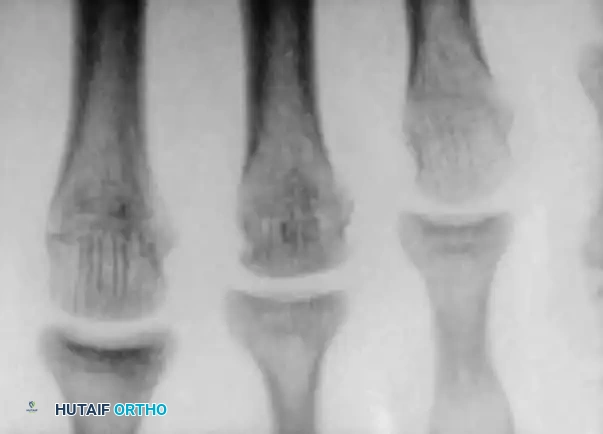

Osteochondritis dissecans (OCD) of the ankle primarily affects the talar dome. The natural history of this lesion in children with open physes is highly favorable compared to adult populations.

Natural History and Imaging

Bauer et al., in a long-term follow-up study (≥ 20 years) of 30 children with ankle osteochondritis, found that only one patient developed severe osteoarthritis. The vast majority experienced complete healing with only minor residual radiographic changes. This is in stark contrast to osteochondritis of the knee, where secondary osteoarthritis is a frequent complication.

Radiographic and MRI evaluation of osteochondral lesions of the talar dome, demonstrating subchondral separation and surrounding edema.